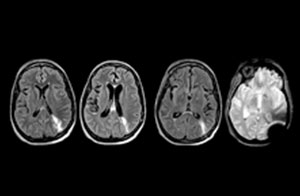

new mri protocols for neuro ed scans

new mri exams in neuro 3